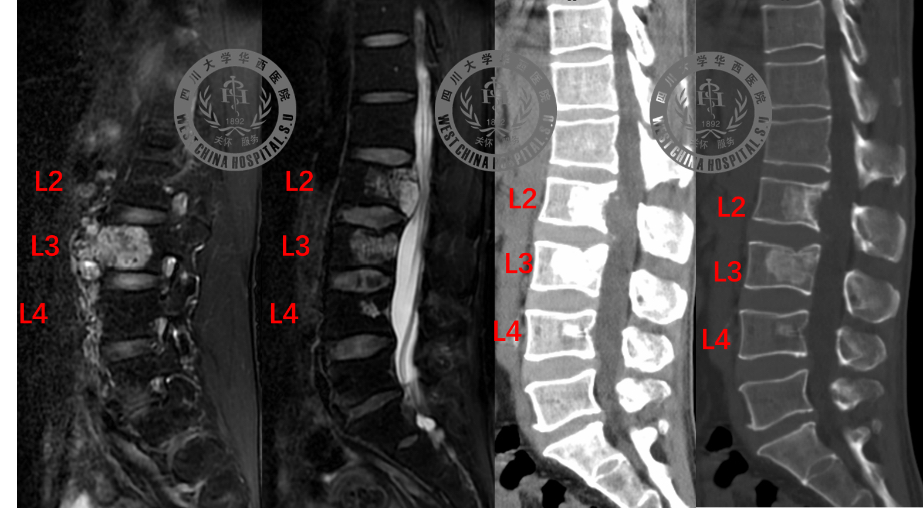

李先生今年47岁,7个月前,因为腰背部疼痛、右股部前外侧麻木疼痛求医。经过一系列检查发现,李先生腰椎第2、3、4椎体长有脊索瘤。

其中,腰2椎肿瘤向椎管内生长,已经压迫椎管内脊髓神经,产生马尾圆锥损害;腰3椎肿瘤向腹腔内生长,形成巨大的软组织肿块。

3D打印人工椎体设计、实物及术后复查图

为实现前方椎体有效重建,李涛教授团队利用3D打印技术生产出个体化人工椎体。它根据患者解剖结构,进行个性化设计,完美契合上下正常椎体连接面。而3D多孔钛合金打印设计,为人工椎体提供了足够的生物力学强度。

复查影像学显示肿瘤无残留,内固定与人工椎体位置良好。李先生已于5月8日顺利出院。